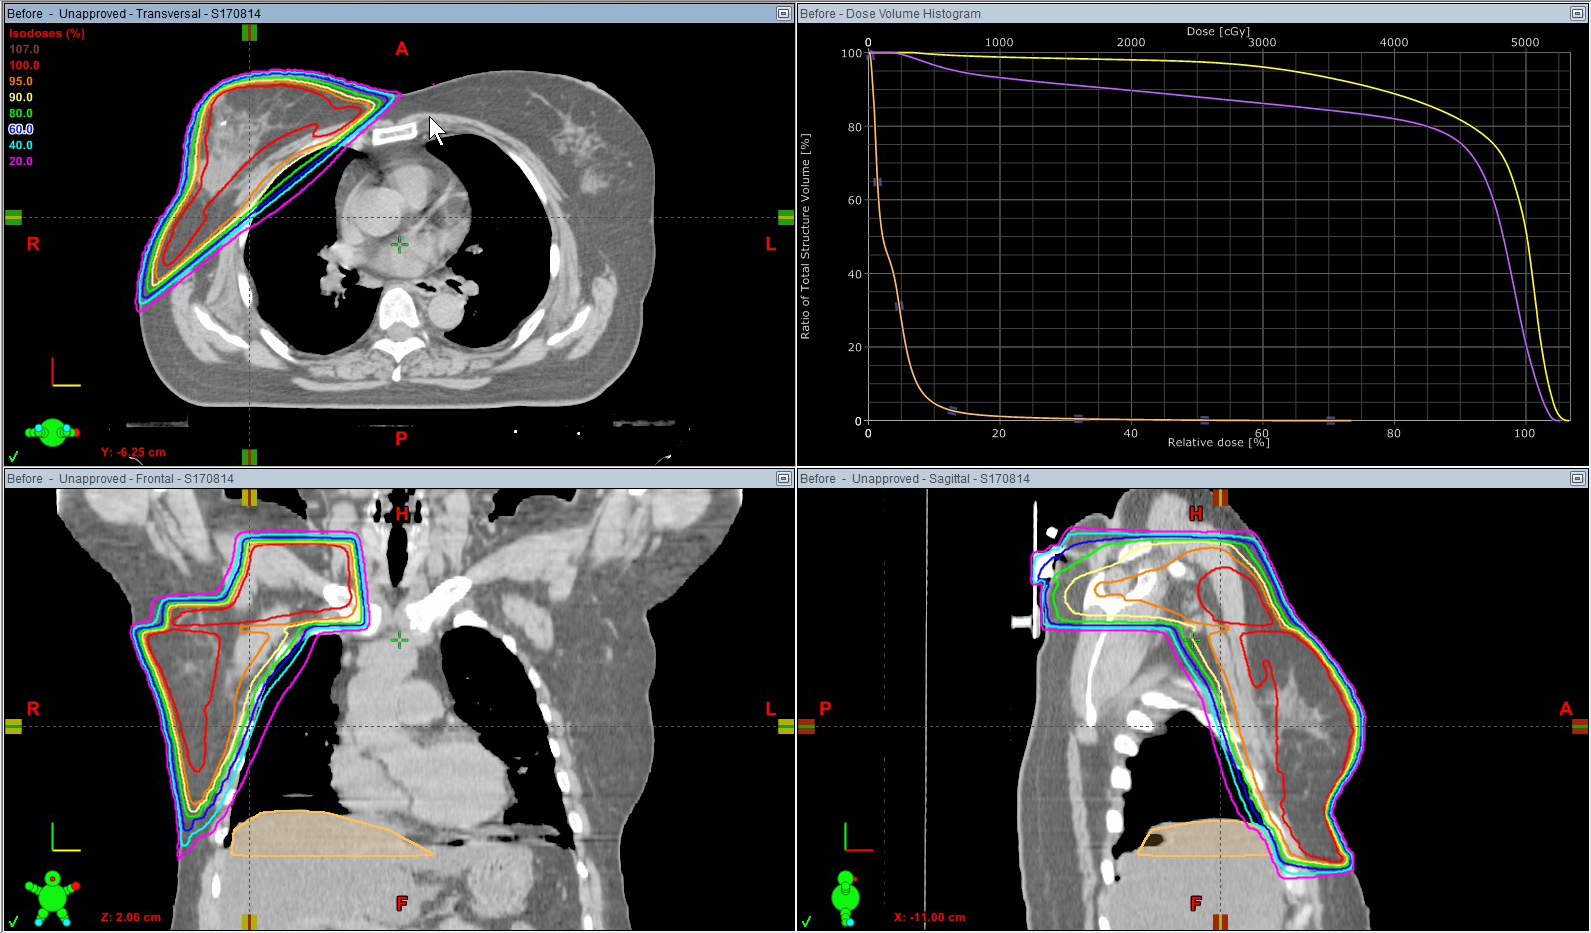

右乳がん 術後照射

66Gy/33回

線量分布図